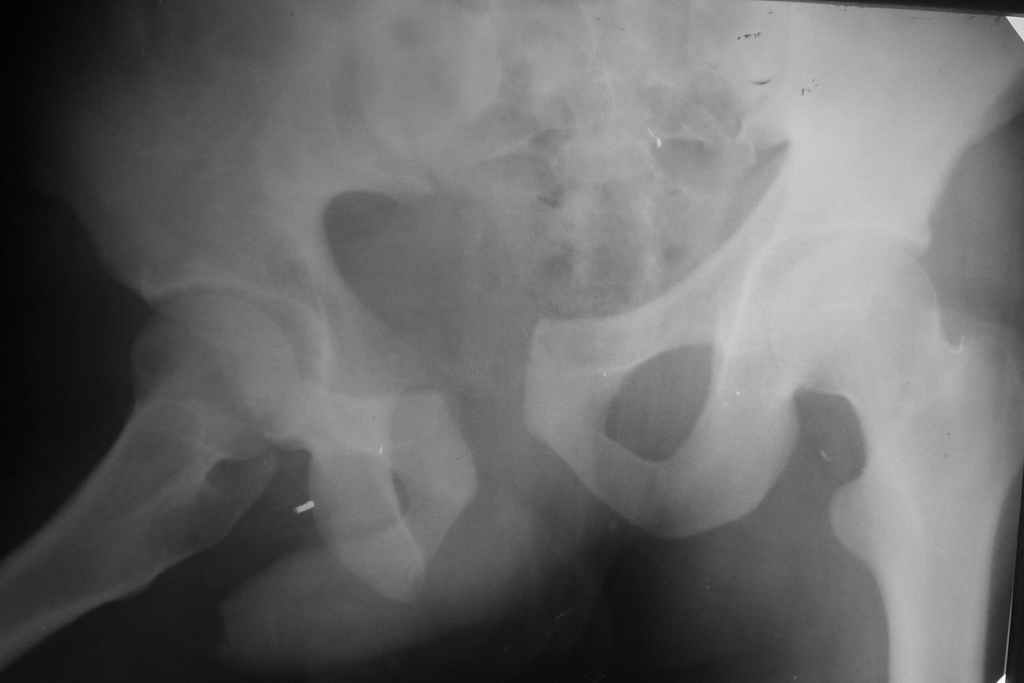

Застарелый перелом таза

Уважаемые коллеги! Вчера оперировал больного с переломом таза месячной давности - разрыв симфиза, перелом обих ветвей лонной кости справа и трансфораминальный перелом крестца справа.

Картинки шлю отдельно. Отрепонировать полностью вертикальное смещение не удалось. Хотел-бы услышать Ваше мнение о допустимости (или недопустимости) подобного стояния отломков и рекомендации по дальнейшей тактике.

Виден разрыв правого крестцово-поздошного сочленения, разрыв симфиза.

Было пока только одно изображение - видимо, фас до операции.

Хотелось бы , конечно, увидеть картинки. Многие авторы считают, что остаточное смещение в задних отеделах не должно превышать 10 мм.